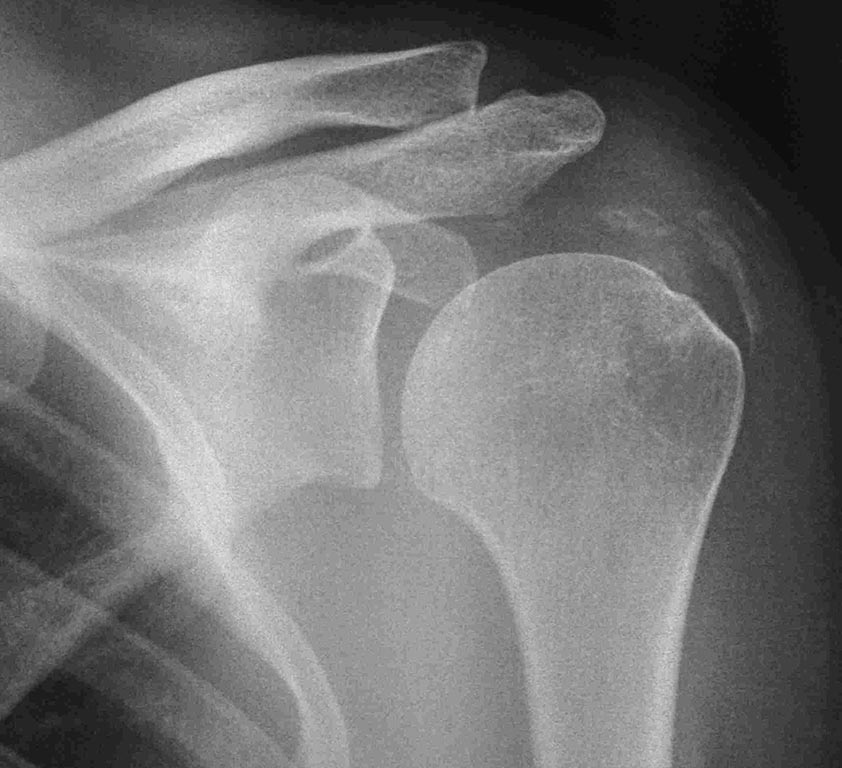

Здравствуйте уважаемые коллеги. вот возник вопрос. больная Е 36 лет

кальцинирующий тендинит с обеих сторон (на рентгенограммах одна

сторона). плотность по КТ 1400. несмотря на это перед тем как идти на

артроскопическое удаление депозита произведена попытка размыть

физраствором. вот что и получилось. объем движений в суставе полностью

восстановлен " на столе" через место депозита 2000мл раствора.